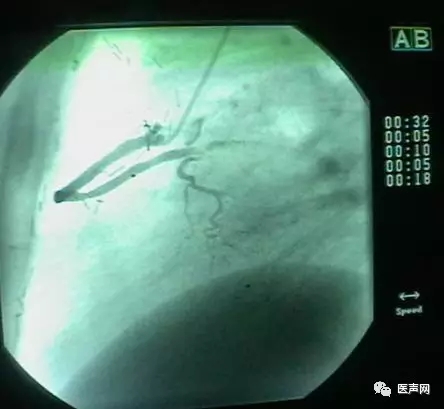

病例6:小血管病变处理---药物涂层球囊+金属裸支架(DCB+BMS)

中间支PCI术后,复查CAG,无ISR。RCA远端90%狭窄,小血管病变,中段40%狭窄 处理:小血管病变处理策略---药物涂层球囊+金属裸支架(DCB+BMS)(附图)

DCB(Eurocro, DIOR):2.5×15@8-10bar,2min

BMS(Motion): 2.5×18@14bar,20sec

药物涂层球囊扩张

支架术后

这是余江涛教授刚刚开始做的新课题,用DCB治疗小血管病变(small vessel lesion)。